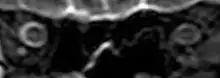

On 2 November 2017, scientists reported that significant changes in the position and structure of the brain have been found in astronauts who have taken trips in space, based on magnetic resonance imaging (MRI) studies. Astronauts who took longer space trips were associated with greater brain changes.[11][12]

Intracranial pressure (ICP) needs to be directly measured before and after long duration flights to determine if microgravity causes the increased ICP. On the ground, lumbar puncture is the standard method of measuring cerebral spinal fluid pressure and ICP,[6][44] but this carries additional risk in-flight.[4] NASA is determining how to correlate ground-based MRI with inflight ultrasound[4] and other methods of measuring ICP in space is currently being investigated.[44]